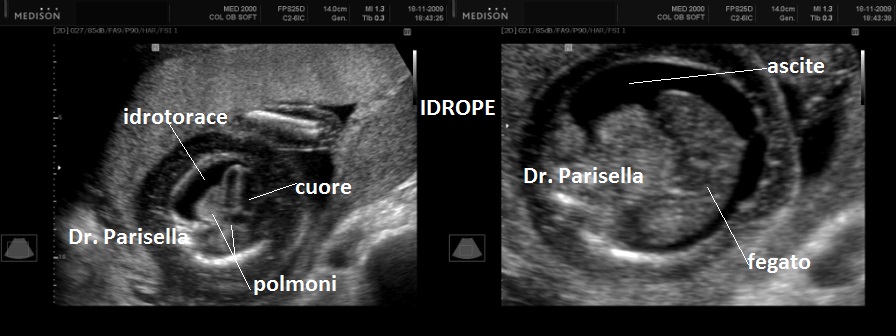

Quella che interessa dal punto di vista della diagnosi ecografica prenatale è l'Osteogenesi Imperfetta tipo II (OMIM 166210) caratterizzata da fragilità ossea con fratture multiple, micromelia severa dovuta alle fratture delle ossa lunghe, ipoplasia toracica severa a volte con fratture costali, ipomineralizzazione diffusa del cranio.  Ecograficamente si manifesta con ossa corte, ricurve e fratturate (le ossa fratturate si presentano angolate); ossa craniche scarsamente ossificate (tanto che la volta cranica può avere una ecogenicità simile a quella della linea mediana) con conseguente migliore evidenza e definizione delle strutture cerebrali e segno caratteristico la deformabilità della teca cranica.;  ipoplasia toracica con fratture costali; IUGR; movimenti fetali scarsi.